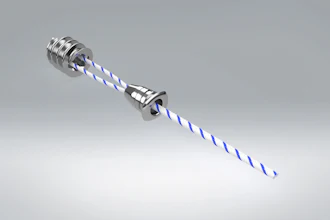

Participants drove a surgical needle through three small holes, first in a virtual simulation and then in a real scenario using the da Vinci Research Kit, an open-source research robot. The exercises mimicked moves needed during surgical procedures on organs in the belly, the researchers said.

Robotic surgery systems provide significant benefits for clinicians by enhancing human skill. They can help surgeons minimize hand tremors and perform fine and precise tasks with enhanced vision.